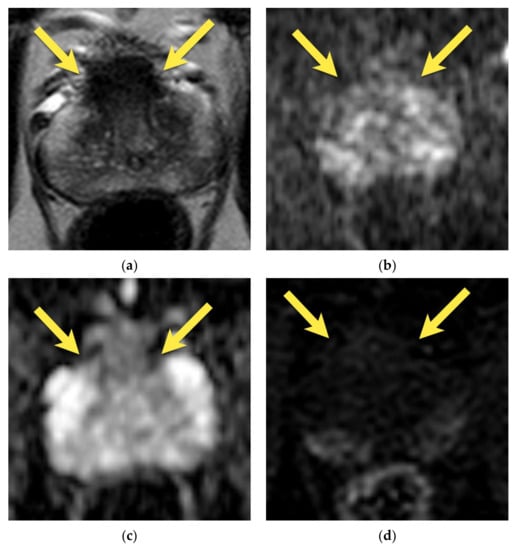

9. Prostatitis